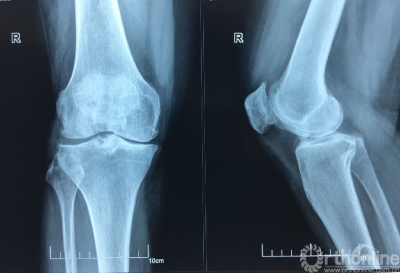

患者杨某患双膝骨性关节炎6年,关节变形,疼痛难忍,近几个月病情加重,5月22日到山医大二院骨科就诊。当得知该院可使用3D打印个性化定制截骨导引板进行胫骨平台高位截骨手术,手术时间只需要20多分钟,且费用是置换人工关节的一半。这一技术保留了患者自身的膝关节,术后能完全恢复自身膝关节的生理功能,而且以后还可以继续做农活时,决定接受3D打印截骨手术。

膝关节骨性关节炎是一种以退行性病理改变为基础的中老年人常见病。对于畸形较轻、较年轻的患者,首选保膝治疗。保膝治疗是一种既可纠正畸形,减轻疼痛,又可保留患者自然的膝关节,最大程度的保留关节的运动功能和舒适性的一种治疗方案,可以延缓关节置换的时间,甚至终身不必置换关节。保膝治疗包括药物治疗、胫骨截骨术和单髁置换术,与全膝关节置换术构成了膝关节骨性关节炎的“阶梯性治疗”,“保膝”和“换膝”并举。根据患者病情发展的不同阶段,畸形程度,年龄和功能需求等因素,提供不同的手术选择,真正做到“精准医疗”。

“高位胫骨截骨手术(HTO)已经开展多年,但是,之前由于手术难度高,如果没有精确的角度、深度、斜率等数据为依据,很可能对患者造成骨折及多项病发症,一般都需要具有丰富经验的临床医生才敢实施手术。”通过相关精密设备采集患者数据,并分析制定出个性化手术方案,打印出手术中导引手术角度、深度等6个精准化数据的导板,手术时间缩短了一半以上,且术后患者不仅膝关节疼痛即刻缓解,2-3天左右就可在适当的护膝辅具下,轻踩试走。高位胫骨截骨手术(HTO)最大限度保留患者机体功能,对于术后生活质量要求高及活动度大的患者,成为很好的选择。